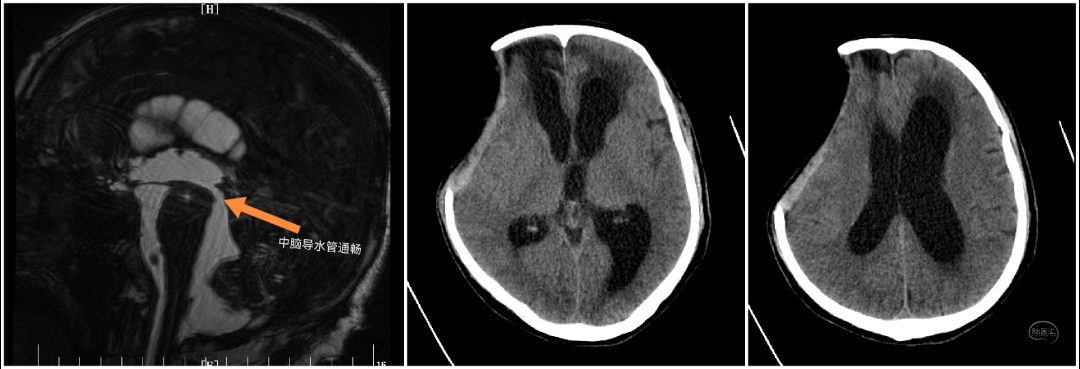

近期陕西省核工业二一五医院神外监护室完成西北首例低颅压性脑积水ProSA+ProGAV系统分流手术。患者老年男性,半年前因重型颅脑损伤在本院行开颅手术治疗,术后意识清楚,好转出院。本次因智力减退步态迟缓10天入院。入院头颅CT及核磁提示(脑室系统扩大,周围可见间质水肿;中脑导水管通畅)。

患者临床症状表现为痴呆、步态不稳、记忆力减退、大小便失禁症状。既往有颅内感染病史,腰穿测压力为70mmH2O,脑脊液蛋白含量高。在颅骨修补手术后,患者意识障碍较前加重。术后头颅CT(脑室系统较前扩大)。采取侧脑室额角穿刺安置Ommaya囊,通过侧脑室穿刺管内水柱高度判断侧脑室内压力,测患者脑室内压力为60mmH2O。诊断为低颅压性脑积水。

针对低颅压脑积水最常用的治疗方法为脑室-腹腔分流术。进行治疗过程中分流管的选择对于患者的预后质量具有重要影响,分流不足与分流过度均会造成严重并发症,不仅影响治疗效果,甚至会导致患者死亡。谢国强主任组织科室研究讨论制定治疗方案。患者脑脊液指标正常后,计划行脑室腹腔分流术。本次选用ProSA+ProGAV系统可调压式分流管为是西北地区首例。proSA是首个允许在直立位,以及在直立位与仰卧位见的任何角度进行开启压力调节的脑积水阀门,其开启压力随患者体位变化而改变。当处于水平体位时,重力装置无阻力,仅压差装置决定整个分流系统的开启压力。处于直立体位时,完整分流系统的开启压力为压差装置开启压力和重力装置开启压力之和。应根据患者身高、体重和年龄选择重力装置的开启压力。它为各种类型的脑积水提供了更多的治疗选项和可能性,大大超越了传统可调压分流管的局限。抗虹吸(抗静水压压力)大小设置可以从0—40cmH2O,适应每位患者的个性化需要。proGAV 因其使用了重力智控阀,其在仰卧位时处于未激活状态,站立位时重力智控阀与可调压阀协同工作,阀门整体开启压力增加,有效的保护了患者避免受到过度引流的影响。proSA可以与不同类型的压差阀组合使用,21级抗虹吸档位可选,与proGAV联合使用可提供高达21*21=441种压力组合。根据患者体位自适应所需开启压力。钛合金的外壳确保高可靠性,避免了外界压力及皮下压力对阀门的影响。手术在脑室镜及腹腔镜辅助下进行,有助于准确定位相应解剖结构,将分流管置于比较理想的位置,从而降低管道被堵塞的机会。术后复查头颅CT可见(脑室较前缩小,间质水肿减轻明显)。